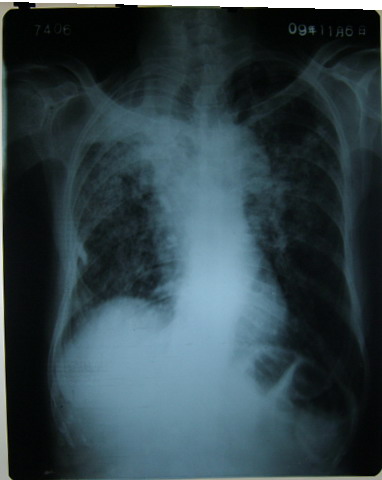

标题: X6526:某女72岁 咳嗽 气短 憋气最近加重 [打印本页]

标题: X6526:某女72岁 咳嗽 气短 憋气最近加重

双侧继发性肺结核……

慢支,肺气肿,双肺继发性结核。

慢支,肺气肿,双肺继发性结核。建议ct除外右上肺合并其它。

慢支,肺气肿,右上结核、肺纤维化并通气不良。

慢支并感染,左肺气肿,双上肺结核待排,建议结合实验室检查或进一步检查。